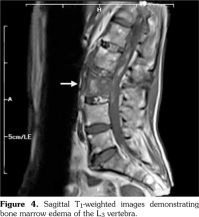

Laboratory assessment before the surgery demonstrated the erythrocyte sedimentation rate as 55 mm/h and C-reactive protein as 43.7 mg/L. Hepatitis markers and Brucella agglutination test were negative. The lumbosacral MRI which was performed before the surgery detected edema at the L3 vertebral corpus, oblique fracture at the L3 vertebral corpus, and 75¥13 mm epidural hematoma through the L1-L3 vertebrae (Figure 3, 4). After the epidural hematoma drainage and decompression surgery, the patient was transferred to the physical medicine and rehabilitation inpatient clinic for the rehabilitation program.